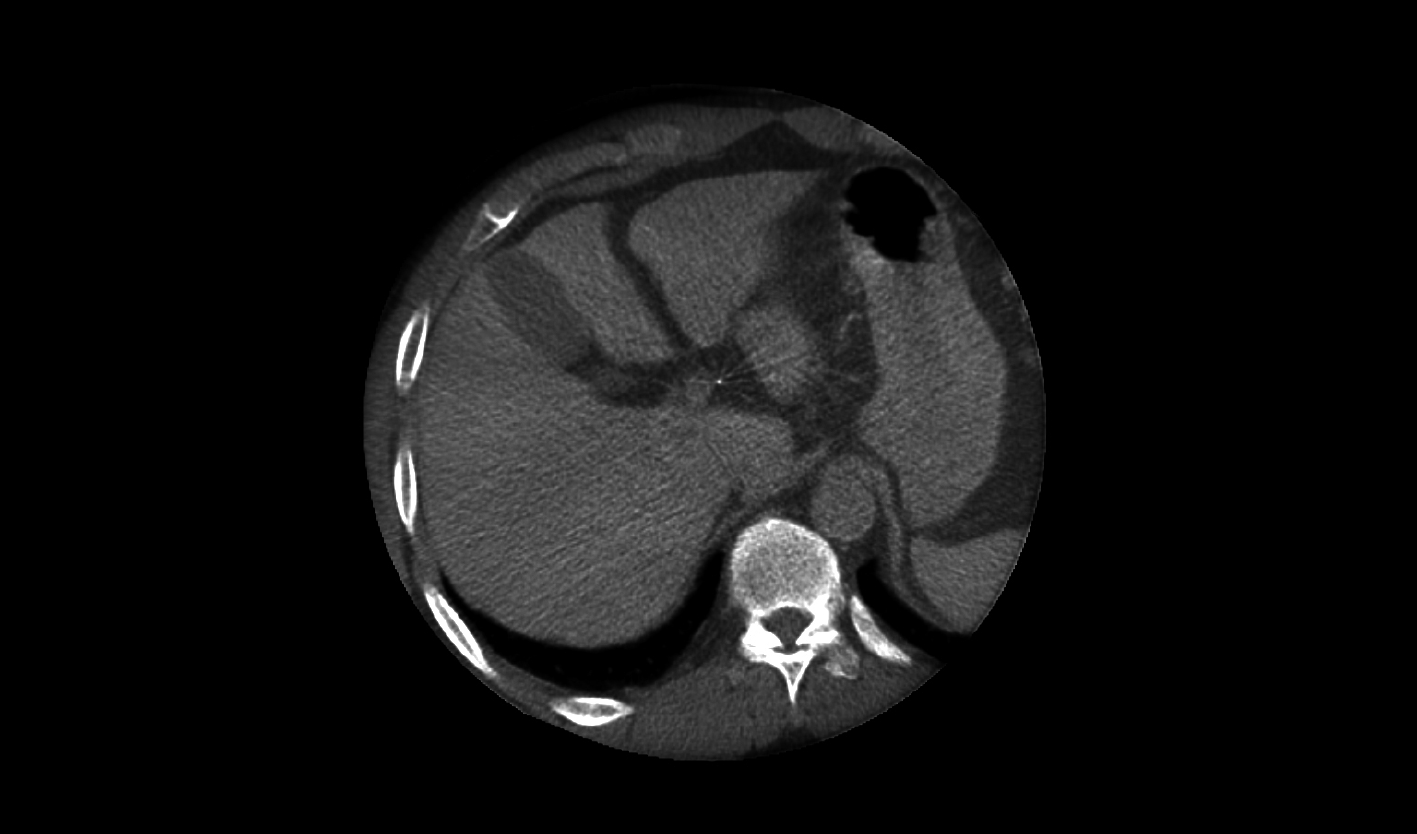

精微小血管可視

2K超清影像鏈,精至微小血管一覽無余

劑量降低

AI+源頭降噪

深度學習多層特征智能降噪,融合多重先進后處理技術,兼顧精準與低劑量